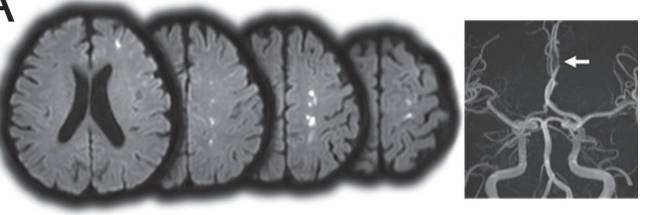

局部分支闭塞合并动脉到动脉栓塞

图6 DWI提示胼胝体及远隔皮层散在梗死灶。CTA提示左侧大脑前动脉A2段重度狭窄。C为模式图,黑色部分为血栓,灰色部分为梗死区,黑色小点即为栓子。